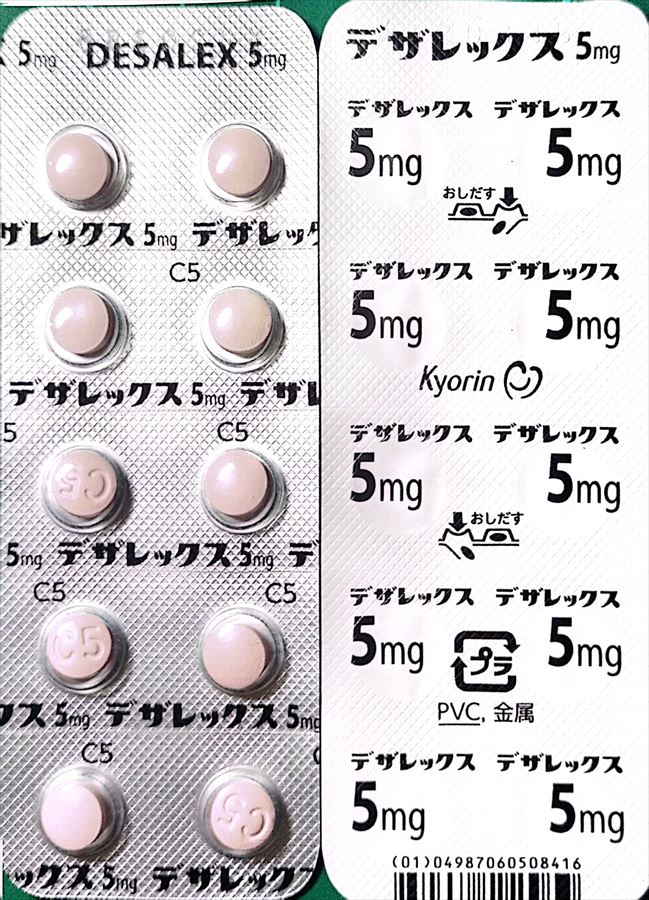

2024.3.9 鼻炎と目のかゆみがひどく、オロパタジン⇒デザレックス&点眼薬 アレジオン に変更 2.10 血液検査結果